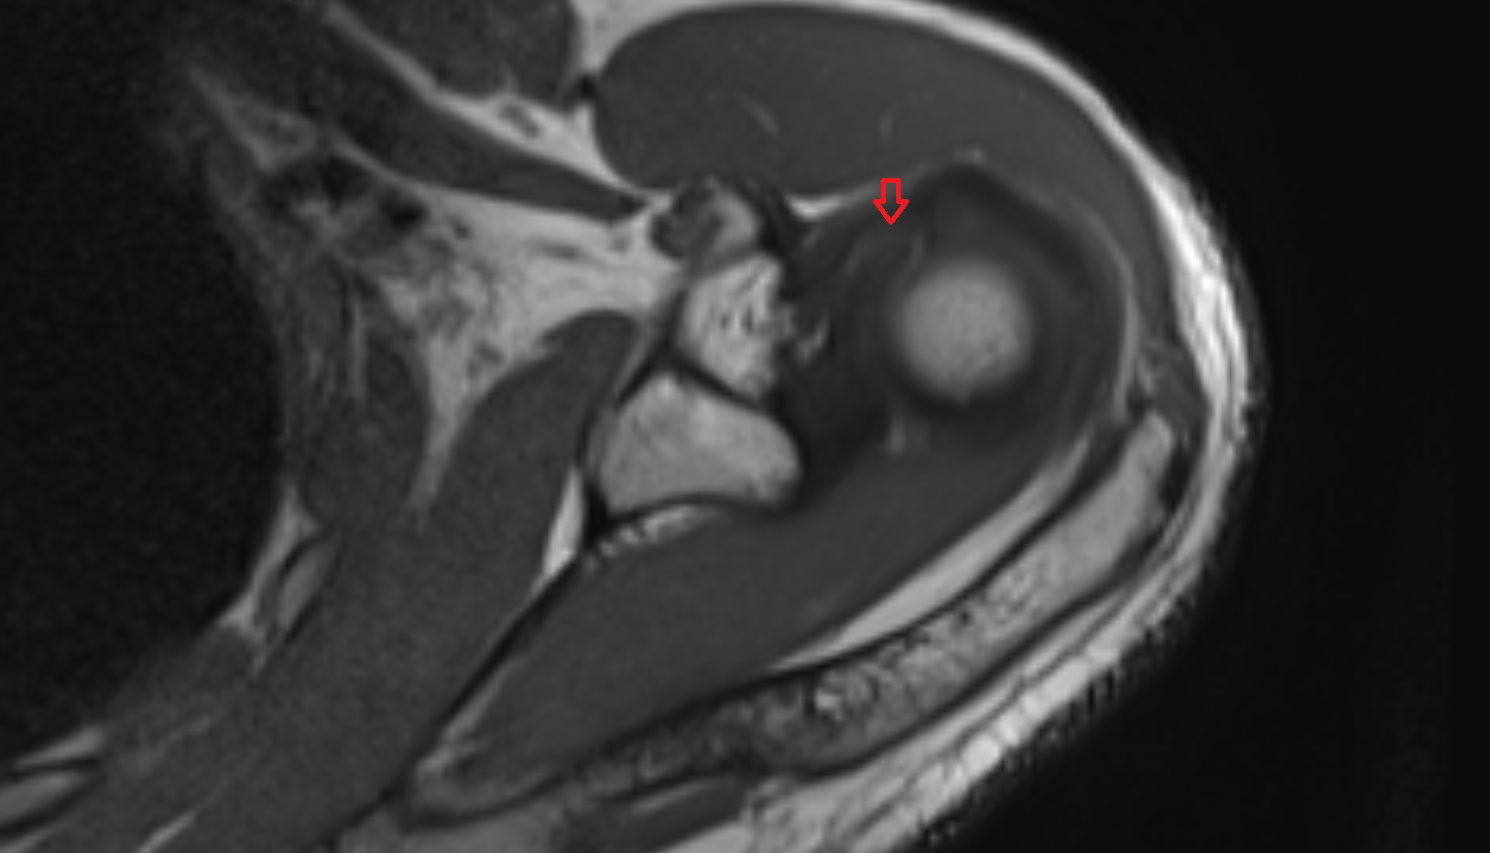

- Glenoid labrum

- Shoulder joint (glenohumeral joint)